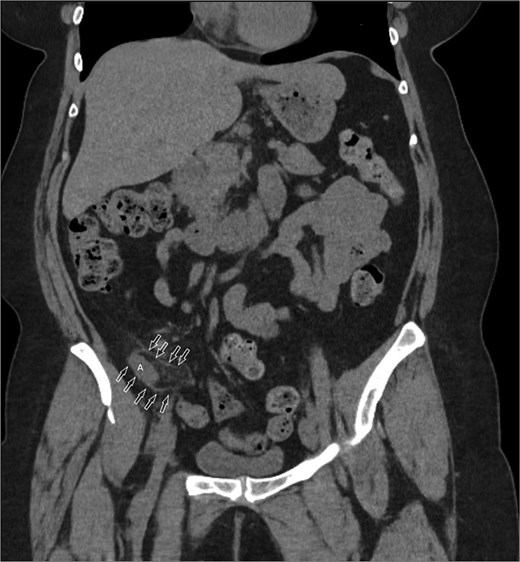

Coronal image CT scan with IV contrast with arrows denoting appendix in proximity to iliacus space. (A) Appendix.